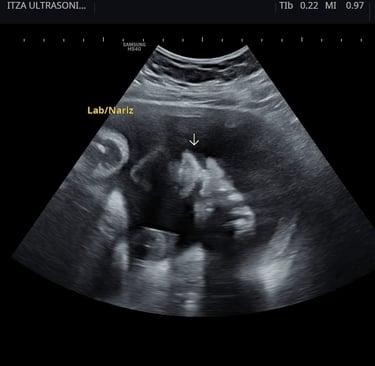

Ultrasonido 2D: el estudio esencial para el control del embarazo

El ultrasonido 2D, en escala de grises, es el más utilizado a lo largo del embarazo. Sirve para:

Aunque su imagen no es tridimensional, es el estudio con mayor valor diagnóstico y el que se recomienda hacer en cada trimestre.